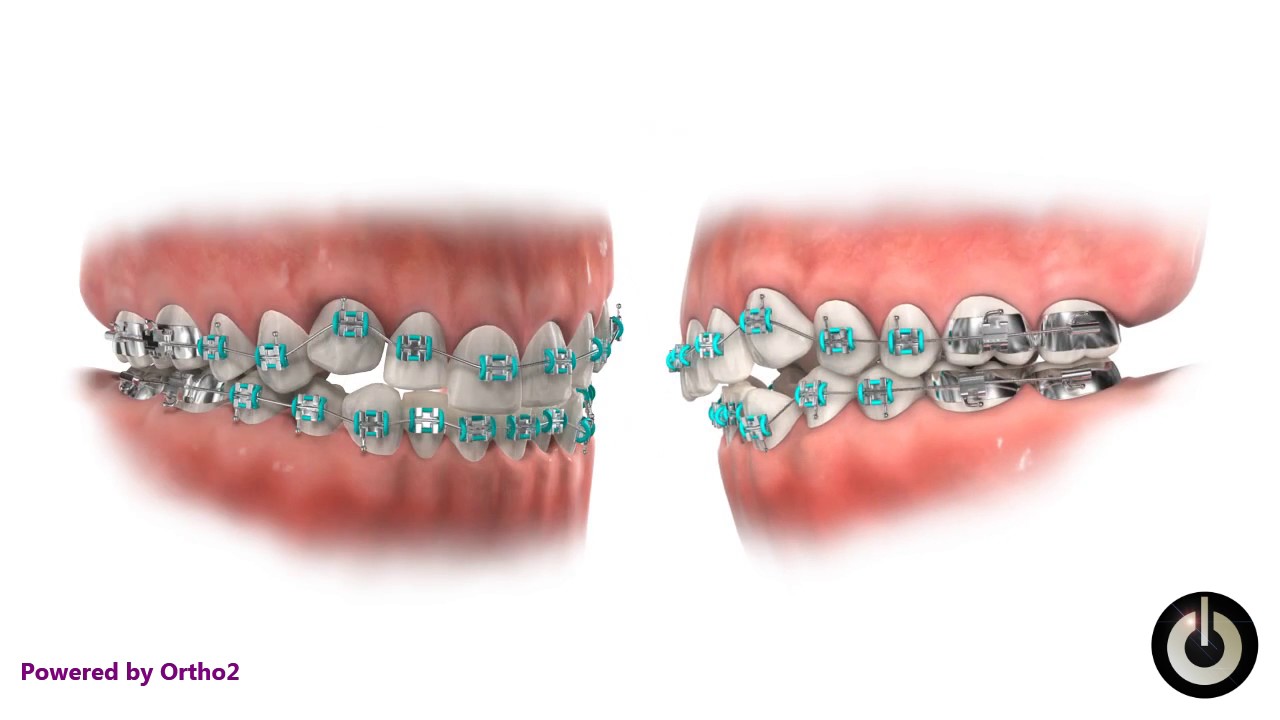

Malocclusion Class I Youtube Class i malocclusion with severe lower anterior crowding and increased overjet treated without extraction. Angle determined that class i malocclusions involve mild crowding and positional or rotational aberrations. class ii malocclusions include the upper incisors creating noticeable “overjet” (tilting outwards) and the upper incisors tilting labially (towards the lips). An overview of the case resulted in the damon ultima psl with variable torques utilized correcting the malocclusion with resolution of the significant crowding and lack of overbite along with substantial arch development. Despite this strong molar connection, patients with class i malocclusion may show additional dental anomalies, such as crowding, spacing, rotations, or misalignment of individual teeth . understanding how and when this malocclusion develops is important to comprehend its etiology.

Class I Crowding Youtube An overview of the case resulted in the damon ultima psl with variable torques utilized correcting the malocclusion with resolution of the significant crowding and lack of overbite along with substantial arch development. Despite this strong molar connection, patients with class i malocclusion may show additional dental anomalies, such as crowding, spacing, rotations, or misalignment of individual teeth . understanding how and when this malocclusion develops is important to comprehend its etiology. Crowding is an increasingly common type of malocclusion caused by a discrepancy in tooth jaw size that leads to twisted and misaligned teeth. two methods to treat this malalignment are tooth material reduction and arch width expansion. Class i malocclusions with severe crowding and tooth size discrepancies may be successfully treated orthodontically with extraction therapy, and co management with other specialists. correction of the discrepancies will optimize occlusal result (overjet, overbite, midline shift, and smile esthetics). Ackerman profitt system of classification involves steps to assess malocclusion. crowding, spacing, cross bite, open bite, deep bite, bimaxillary protrusion, rotations, and other dental problems are discussed, along with their causes and management options. Despite all this, treatment results do not always remain stable. the most common type of malocclusion in mixed dentition patients is crowding. it occurs when there is a discrep ancy between the size of the tooth mass and the size of the supporting bony bases. two treatment strategies used to correct this problem are extraction and expan sion.

Crowding Youtube Crowding is an increasingly common type of malocclusion caused by a discrepancy in tooth jaw size that leads to twisted and misaligned teeth. two methods to treat this malalignment are tooth material reduction and arch width expansion. Class i malocclusions with severe crowding and tooth size discrepancies may be successfully treated orthodontically with extraction therapy, and co management with other specialists. correction of the discrepancies will optimize occlusal result (overjet, overbite, midline shift, and smile esthetics). Ackerman profitt system of classification involves steps to assess malocclusion. crowding, spacing, cross bite, open bite, deep bite, bimaxillary protrusion, rotations, and other dental problems are discussed, along with their causes and management options. Despite all this, treatment results do not always remain stable. the most common type of malocclusion in mixed dentition patients is crowding. it occurs when there is a discrep ancy between the size of the tooth mass and the size of the supporting bony bases. two treatment strategies used to correct this problem are extraction and expan sion.